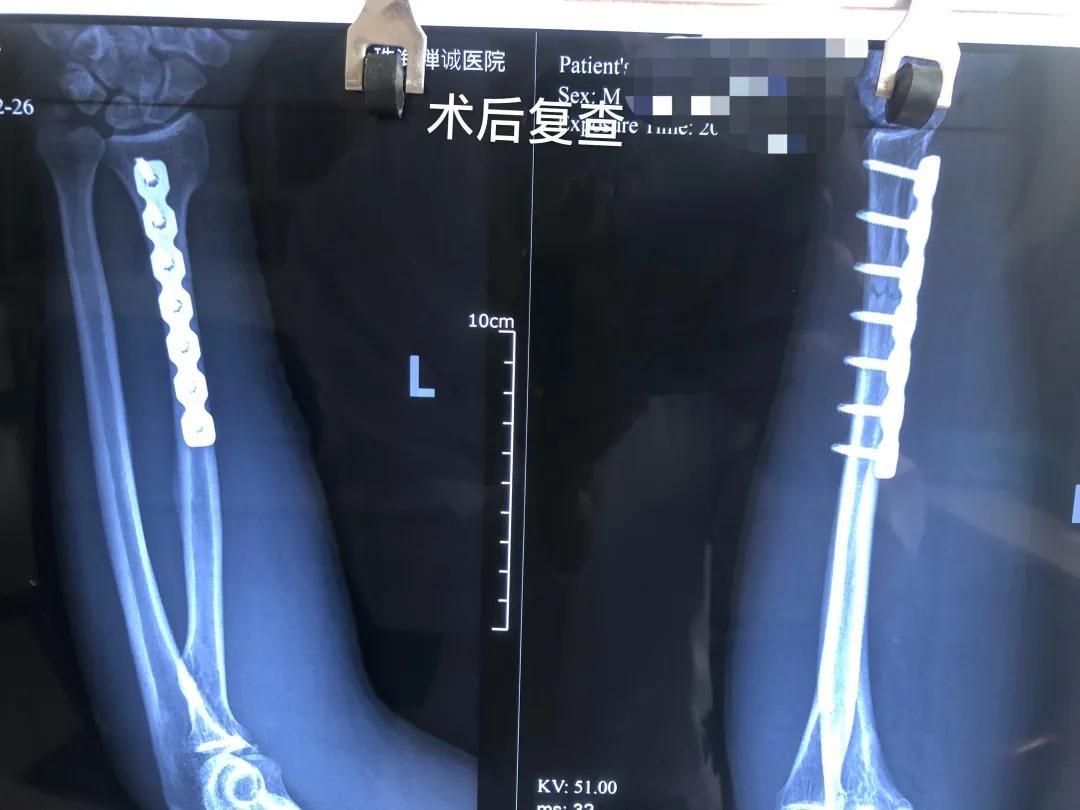

张先生的术后X光片